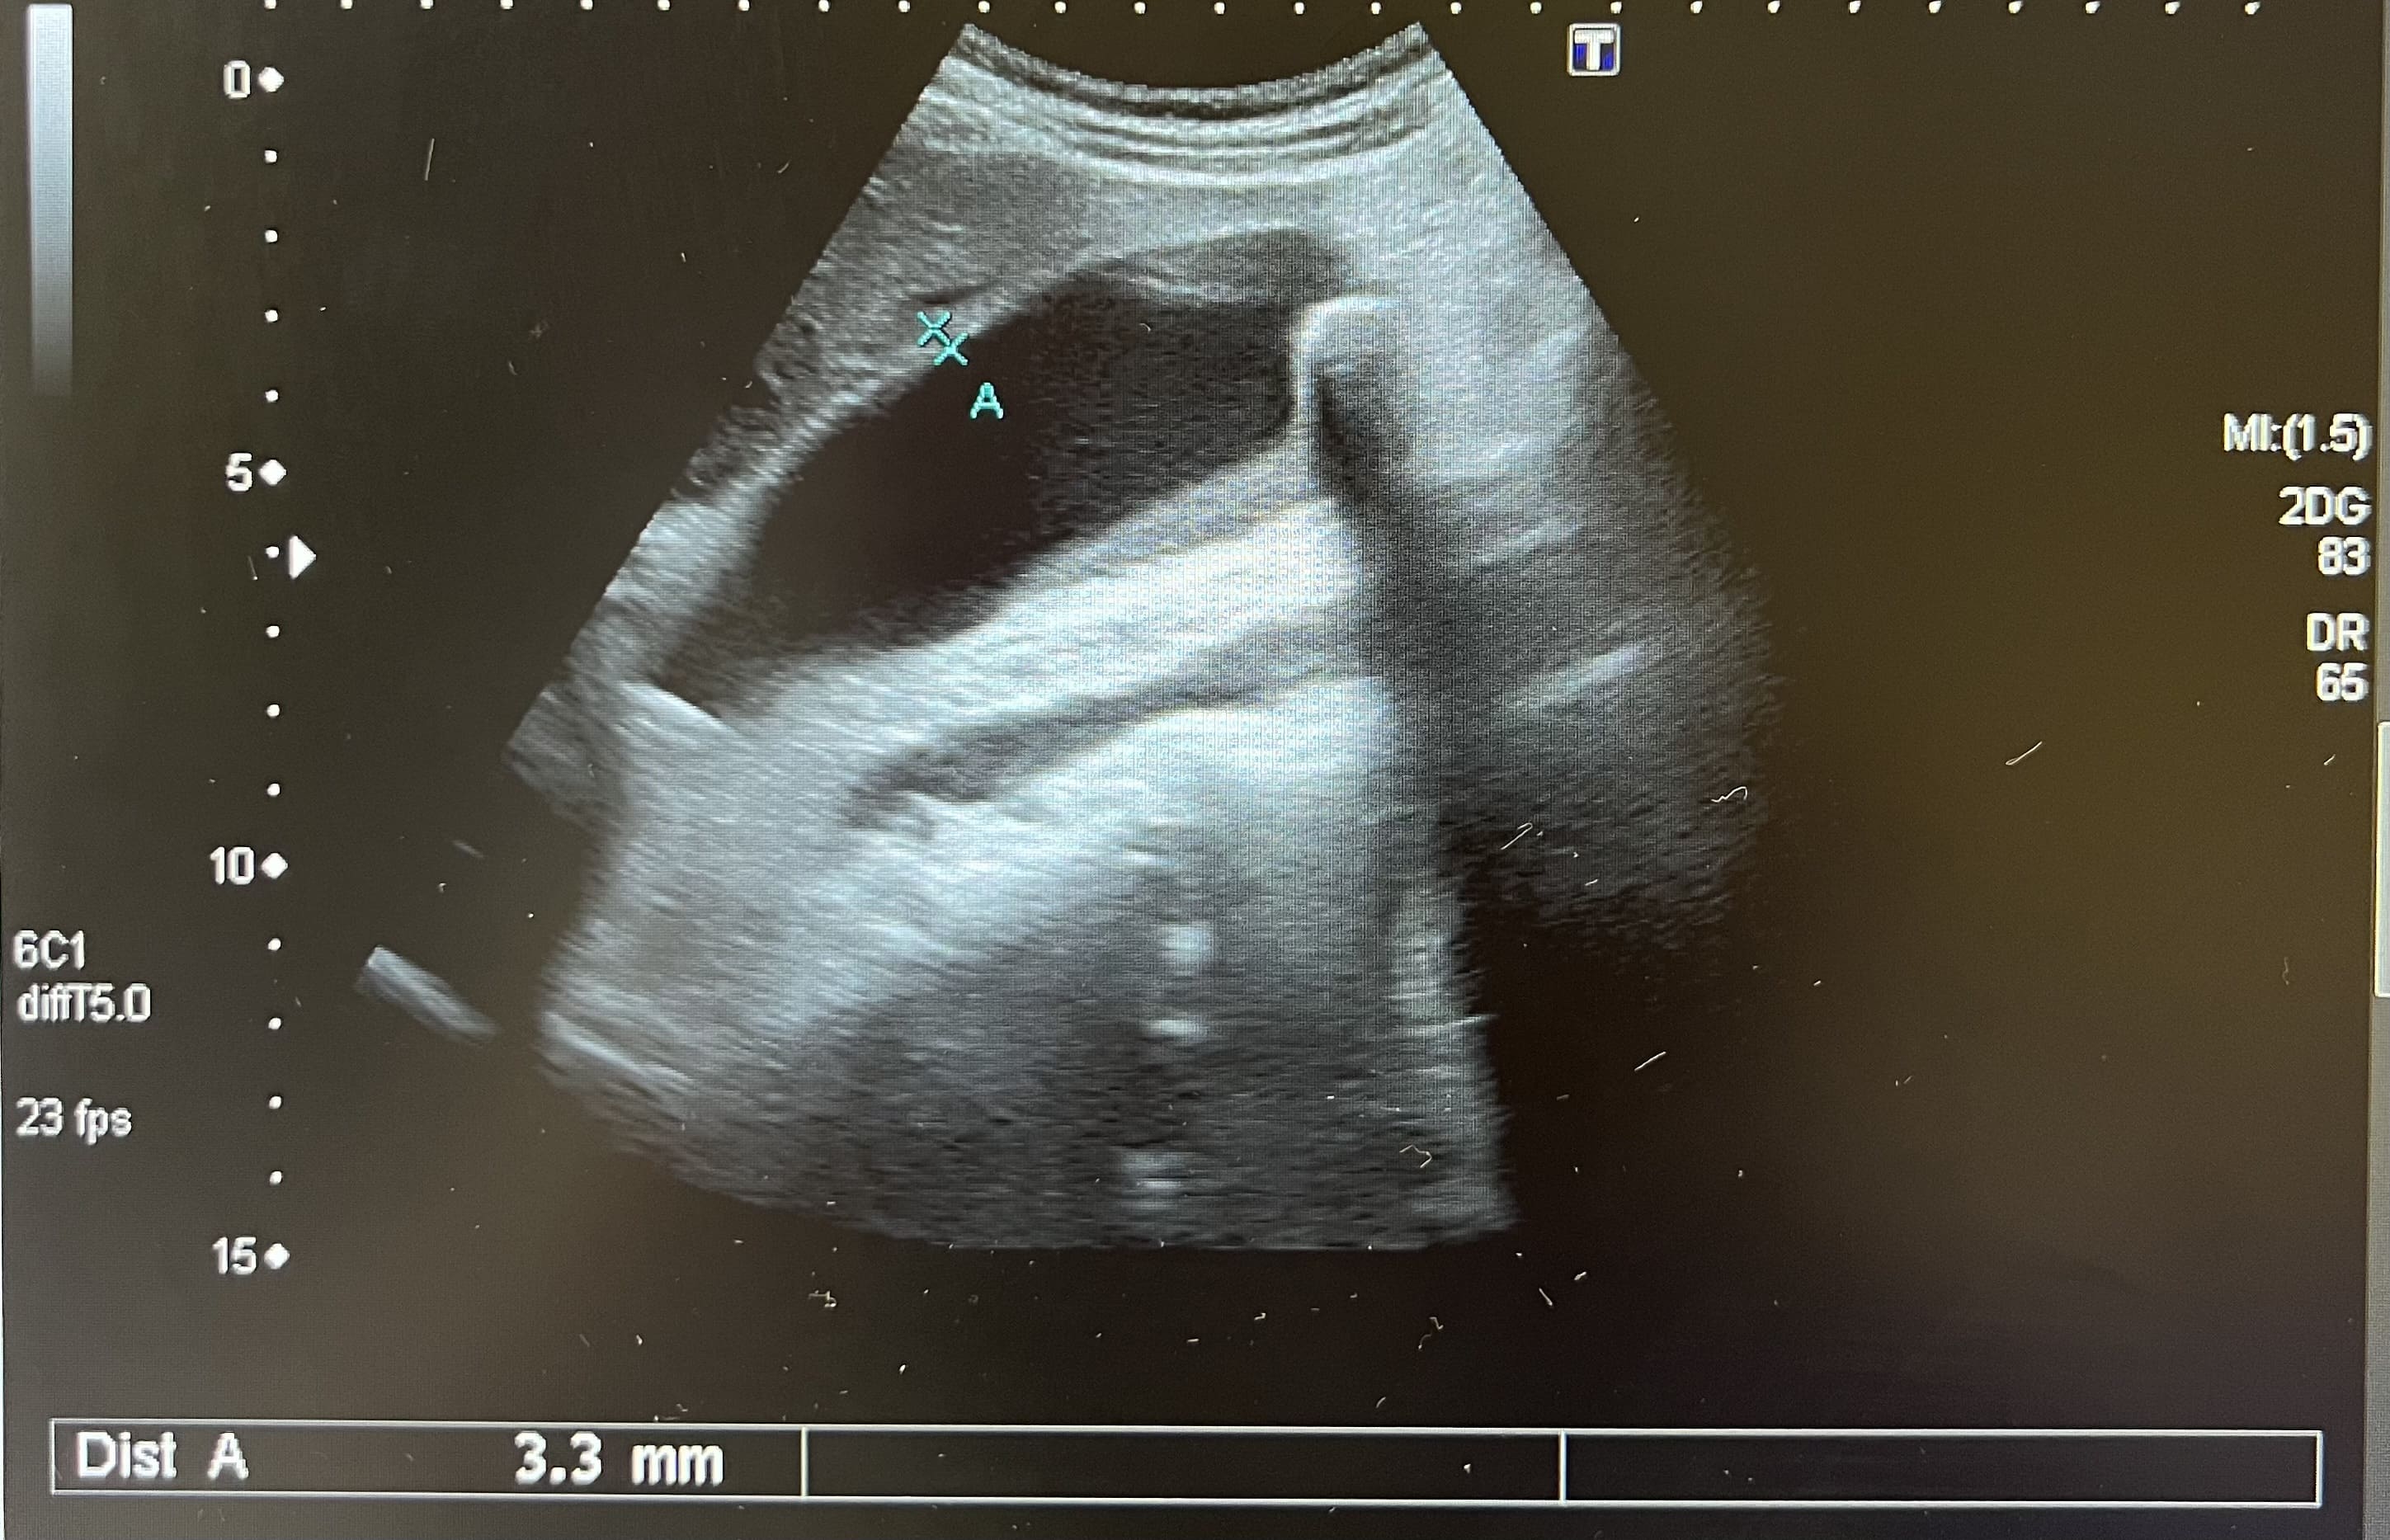

Pruebas complementarias: analítica normal. La ecografía abdominal muestra múltiples imágenes ecogénicas bien definidas en ambos lóbulos, de tamaño variable. Vesícula biliar con dos litiasis subcentimétricas y discreto edema de pared compatible con colecistitis. Estos hallazgos se confirman mediante la realización de una ecografía reglada por parte de radiología.

Juicio clínico: Hemangiomas hepáticos. Colecistitis.

Diagnóstico diferencial: con otras lesiones focales sólidas del hígado. La imagen ecográfica del hemangioma es de una o varias lesiones hiperecogénicas bien definidas que no captan Doppler. La hiperplasia nodular focal se presenta como una lesión hipo o isoecoica que puede captar Doppler. El adenoma se presenta como una masa hiper o hipoecoica con áreas anecoicas, mostrando el Doppler un tumor hipervascular. El hepatocarcinoma tiene un aspecto ecográfico variable, como masa o nódulos hipoecoicos, mal diferenciados e hipervascularizados. Las metástasis hepáticas se suelen presentar como múltiples lesiones sólidas de tamaño y ecogenicidad variables y la presencia de un halo hipoecoico rodeando la masa.

El hemangioma hepático es el tumor hepático benigno más frecuente, con mayor prevalencia en mujeres. Se suelen presentar en forma de lesión única, aunque pueden aparecer en forma de lesiones múltiples, con un tamaño normalmente inferior a 30 milímetros. Suele ser un hallazgo casual, al ser asintomáticos. El diagnóstico diferencial se realiza con otras lesiones hepáticas sólidas y se recomienda un seguimiento ecográfico para confirmar estabilidad.